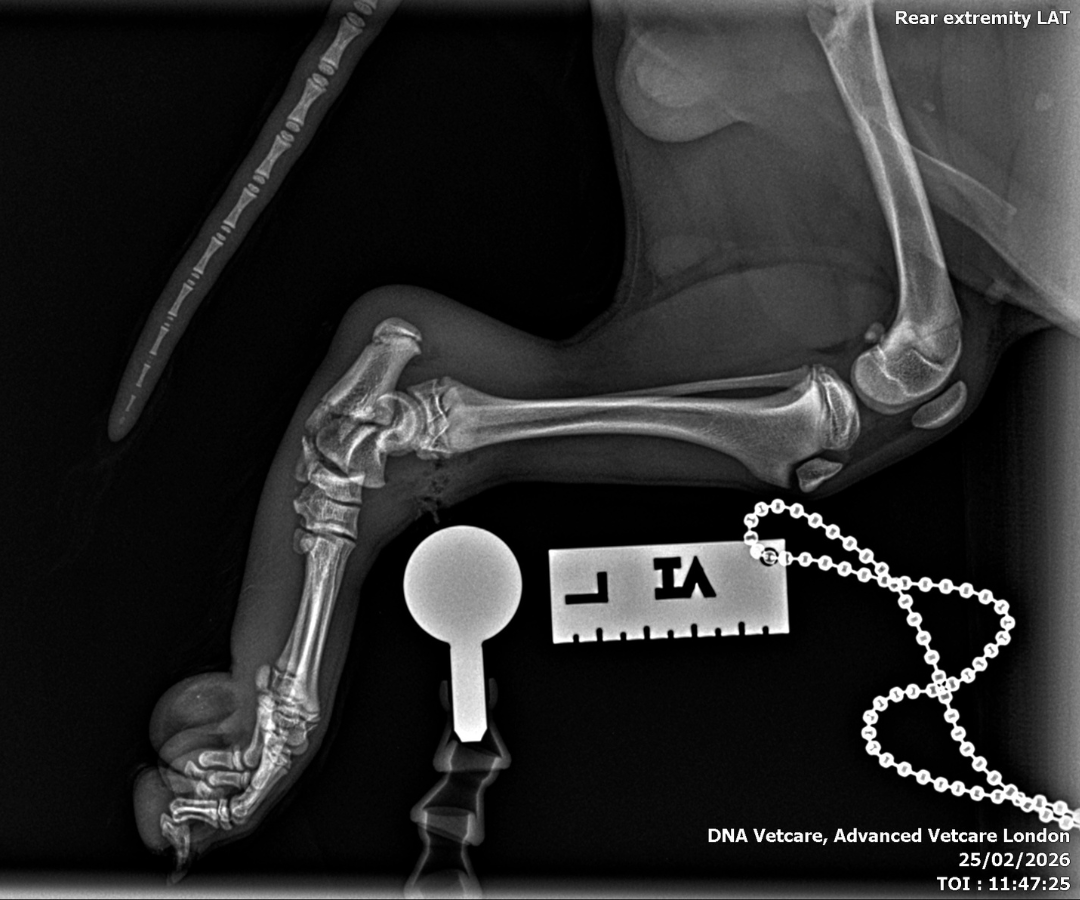

X-rays and cone beam CT of Ralphie's left hindlimb - a technique that uses a cone-shaped beam to produce detailed 3D images, particularly useful in complex orthopaedic cases like this - revealed a combination of injuries that, together, posed a serious surgical challenge:

- A comminuted fracture of the base of the left calcaneus (heel bone), meaning that the bone had broken into multiple fragments

- A small avulsion fracture in the calcaneoquartal region, whereby a small piece of bone had been pulled away from the joint when it was suddenly pulled by the long plantar ligament

- Dislocation of the talo-calcaneal joint - the lower ankle joint that connects the top ankle bone to the heel bone

- Plantar and lateral dislocation of the talocentral joint - this meant that the ligaments holding the bones in the hind leg together had completely torn, and the main hinge joint had broken, causing the paw to collapse toward the ground (plantar) and shift outward toward the side (lateral).